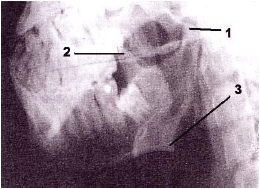

Observe atentamente a figura abaixo e, em seguida, responda à questão.

Trata-se de imagem radiográfica correspondente à incidência de

A

Schüler.

B

Breton.

C

Bellot.

D

Hirtz.